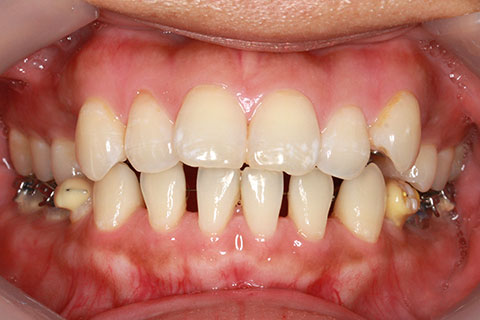

症例

治療前

治療中

治療後

- 年齢・性別

- 30歳女性

- 治療期間

- 3年0ヶ月

- 抜歯

- 上下左右4番抜歯

- 治療費

- 110万円

- 備考

- マルチブラケットを用いた矯正治療

- 治療内容

- 上下顎前突を4本抜歯にて矯正治療

- 施術の副作用(リスク)

- 表側矯正と比較して、歯根の角度を確立する「トルク」の力がかかりにくい。